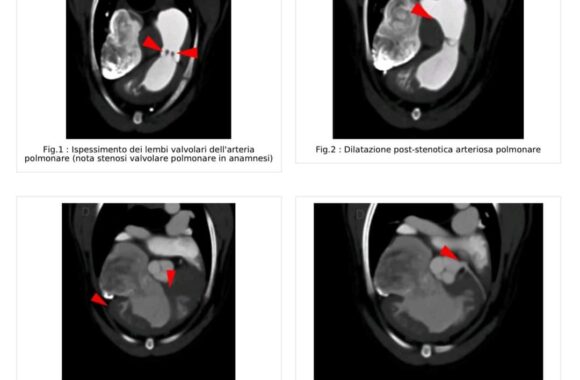

Il Servizio Tac Veterinaria a Portici

Attualmente l’unica clinica veterinaria di Napoli e provincia che ha a disposizione una TAC Multistrato da 128 strati in struttura, ultra veloce (total body in meno di 15 sec.), con refertazione in 24h/48h.